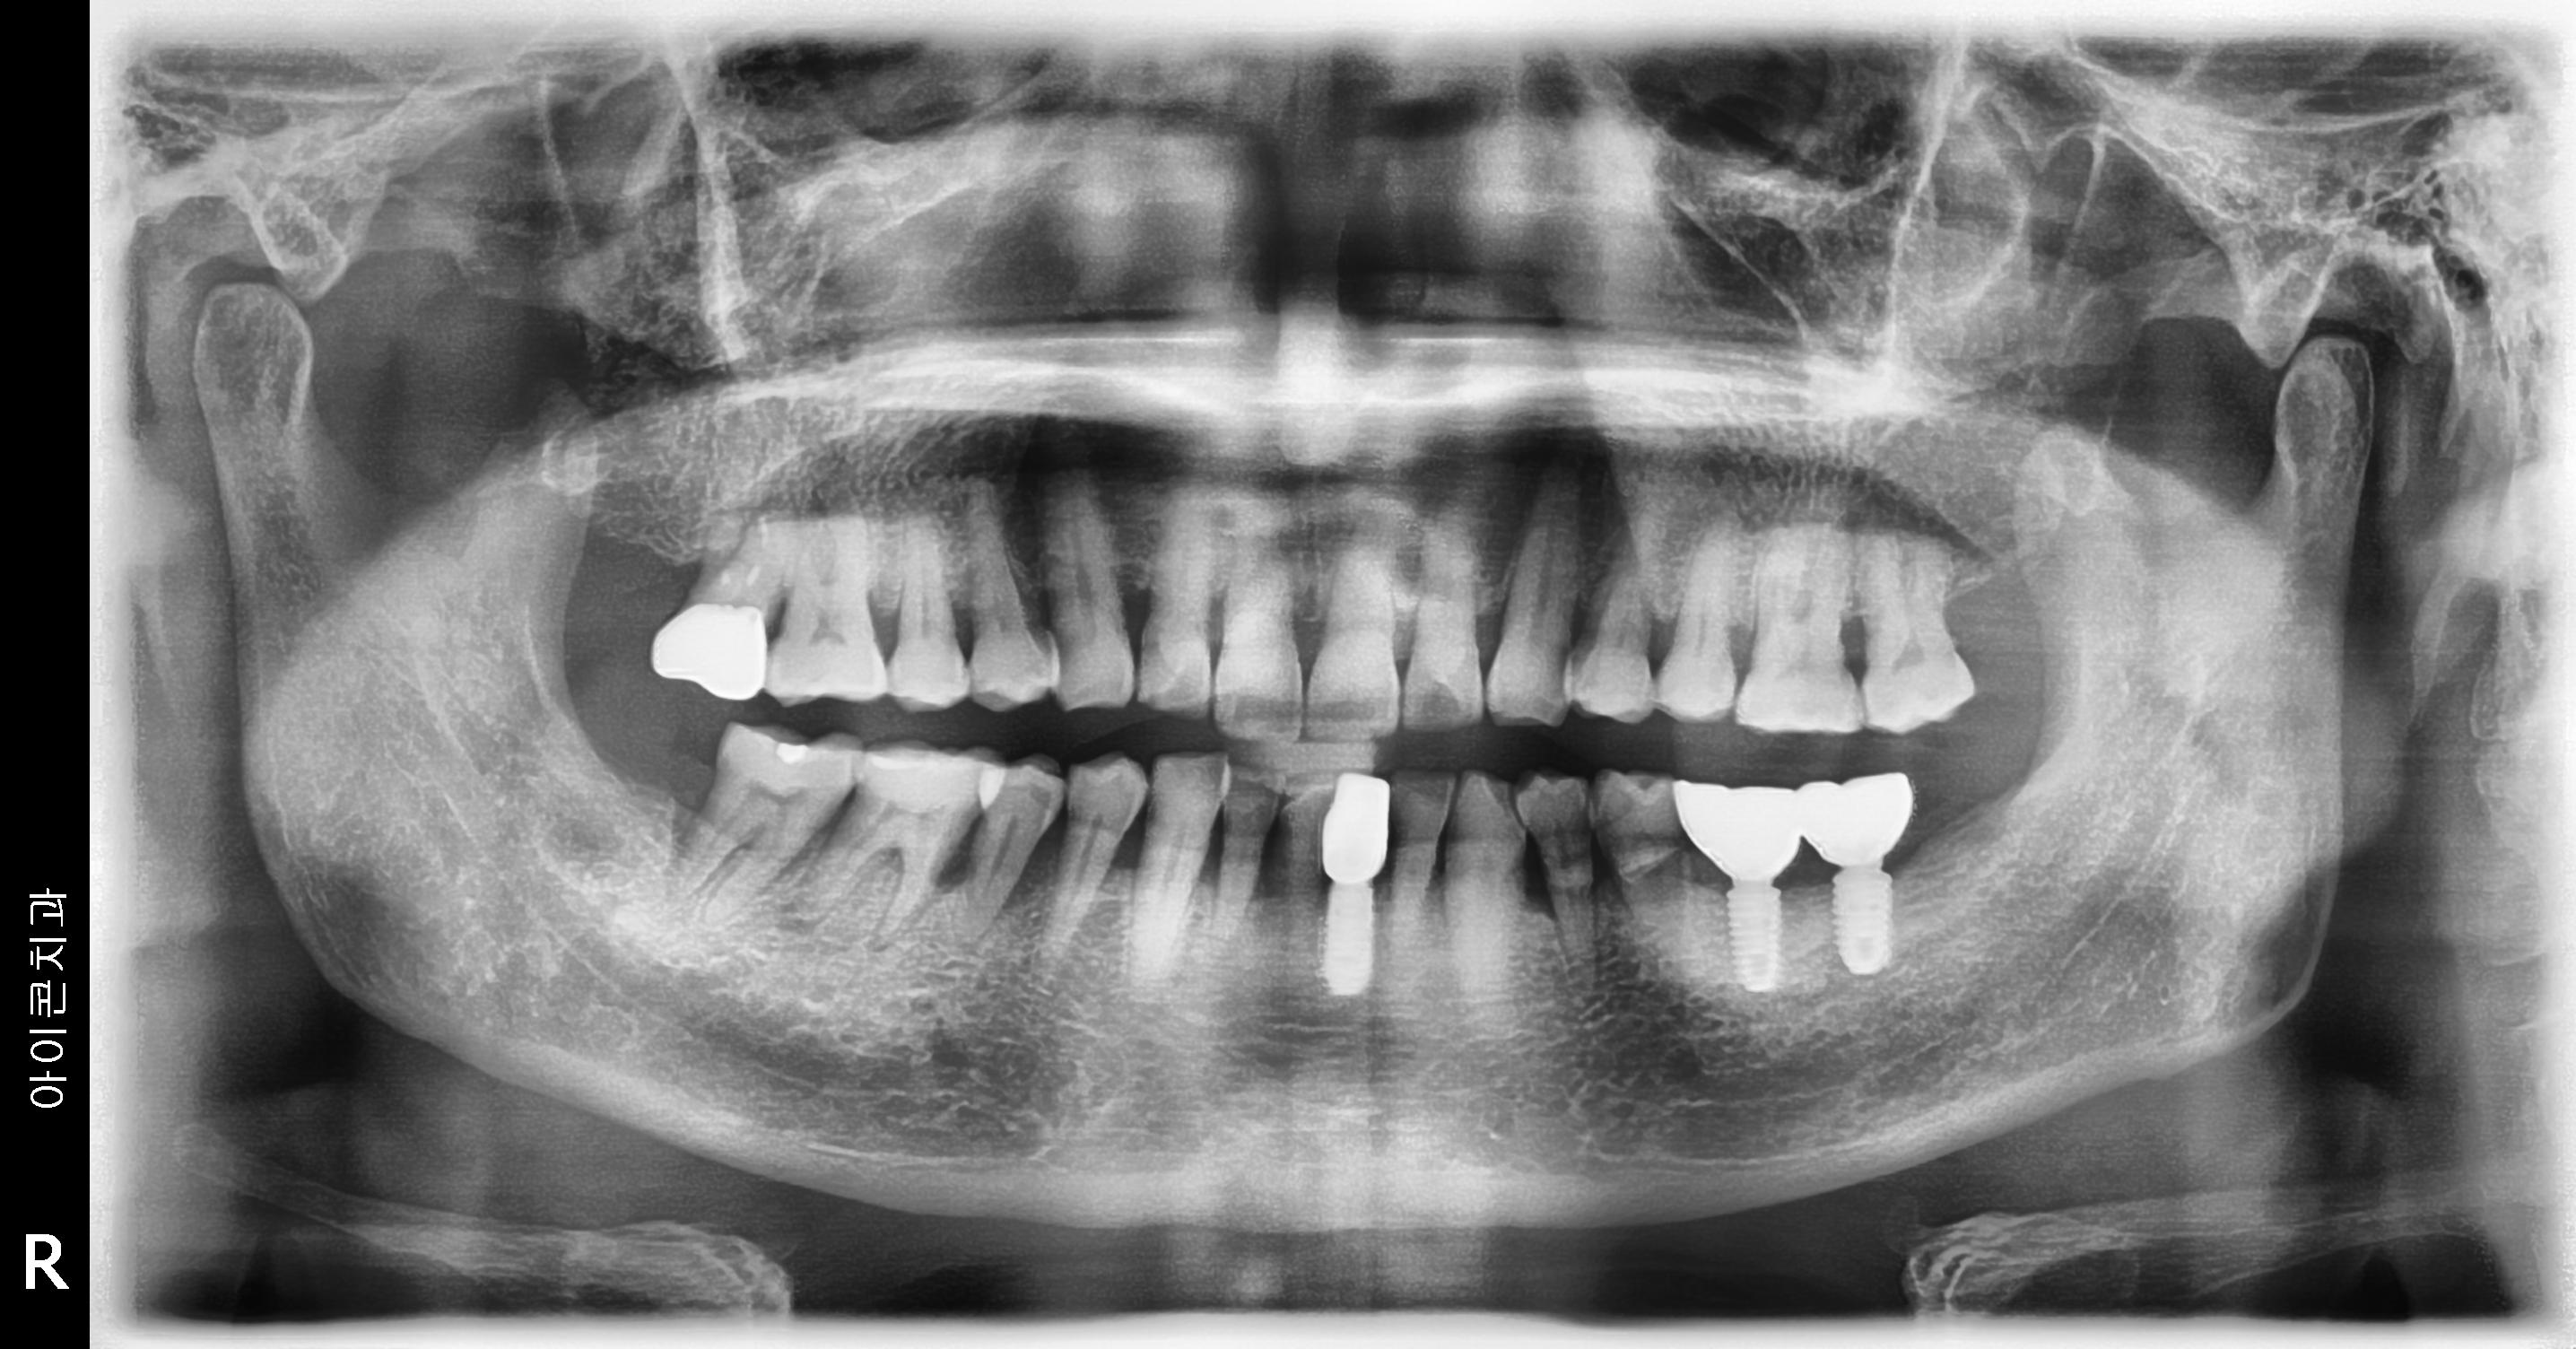

수술 전

수술 후

하악 임플란트 식립사례

전후사진